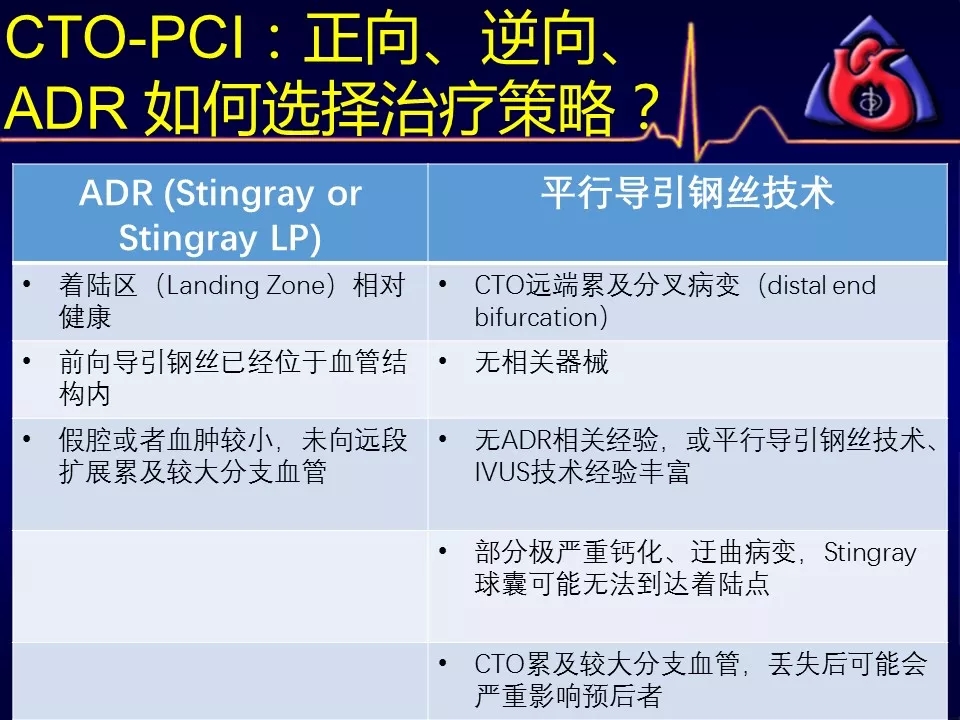

如何选择正向、逆向、IVUS指引及ADR技术?